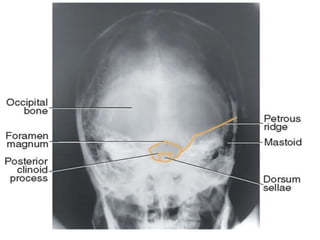

3. Townes.

• The patient faces the x-ray tube, with the chin tucked in

so that the base line is at the right angled to the table.

CRANIUM.

3. Townes cont;

• To achieve this, it may be sometimes be necessary to

place a pad under the occiput or to angle the table

slightly.

• The MSP must be at right angles to table.

• Centre; 5 cm above the glabella, with the tube angled

30°caudad.